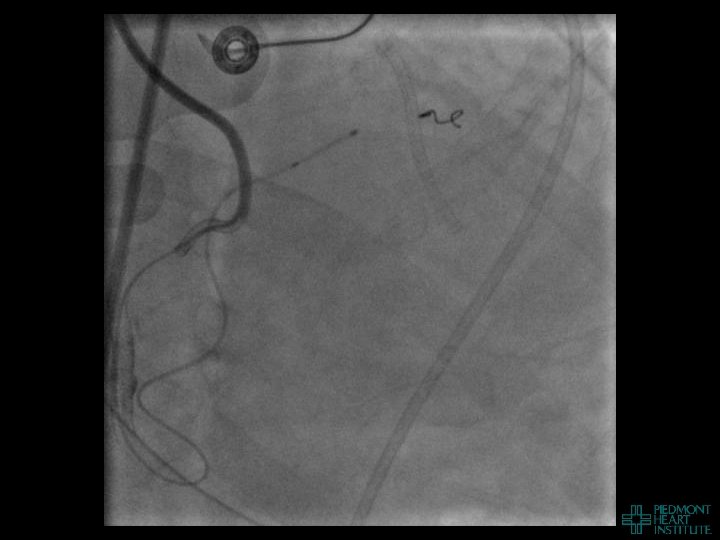

Case Example 2